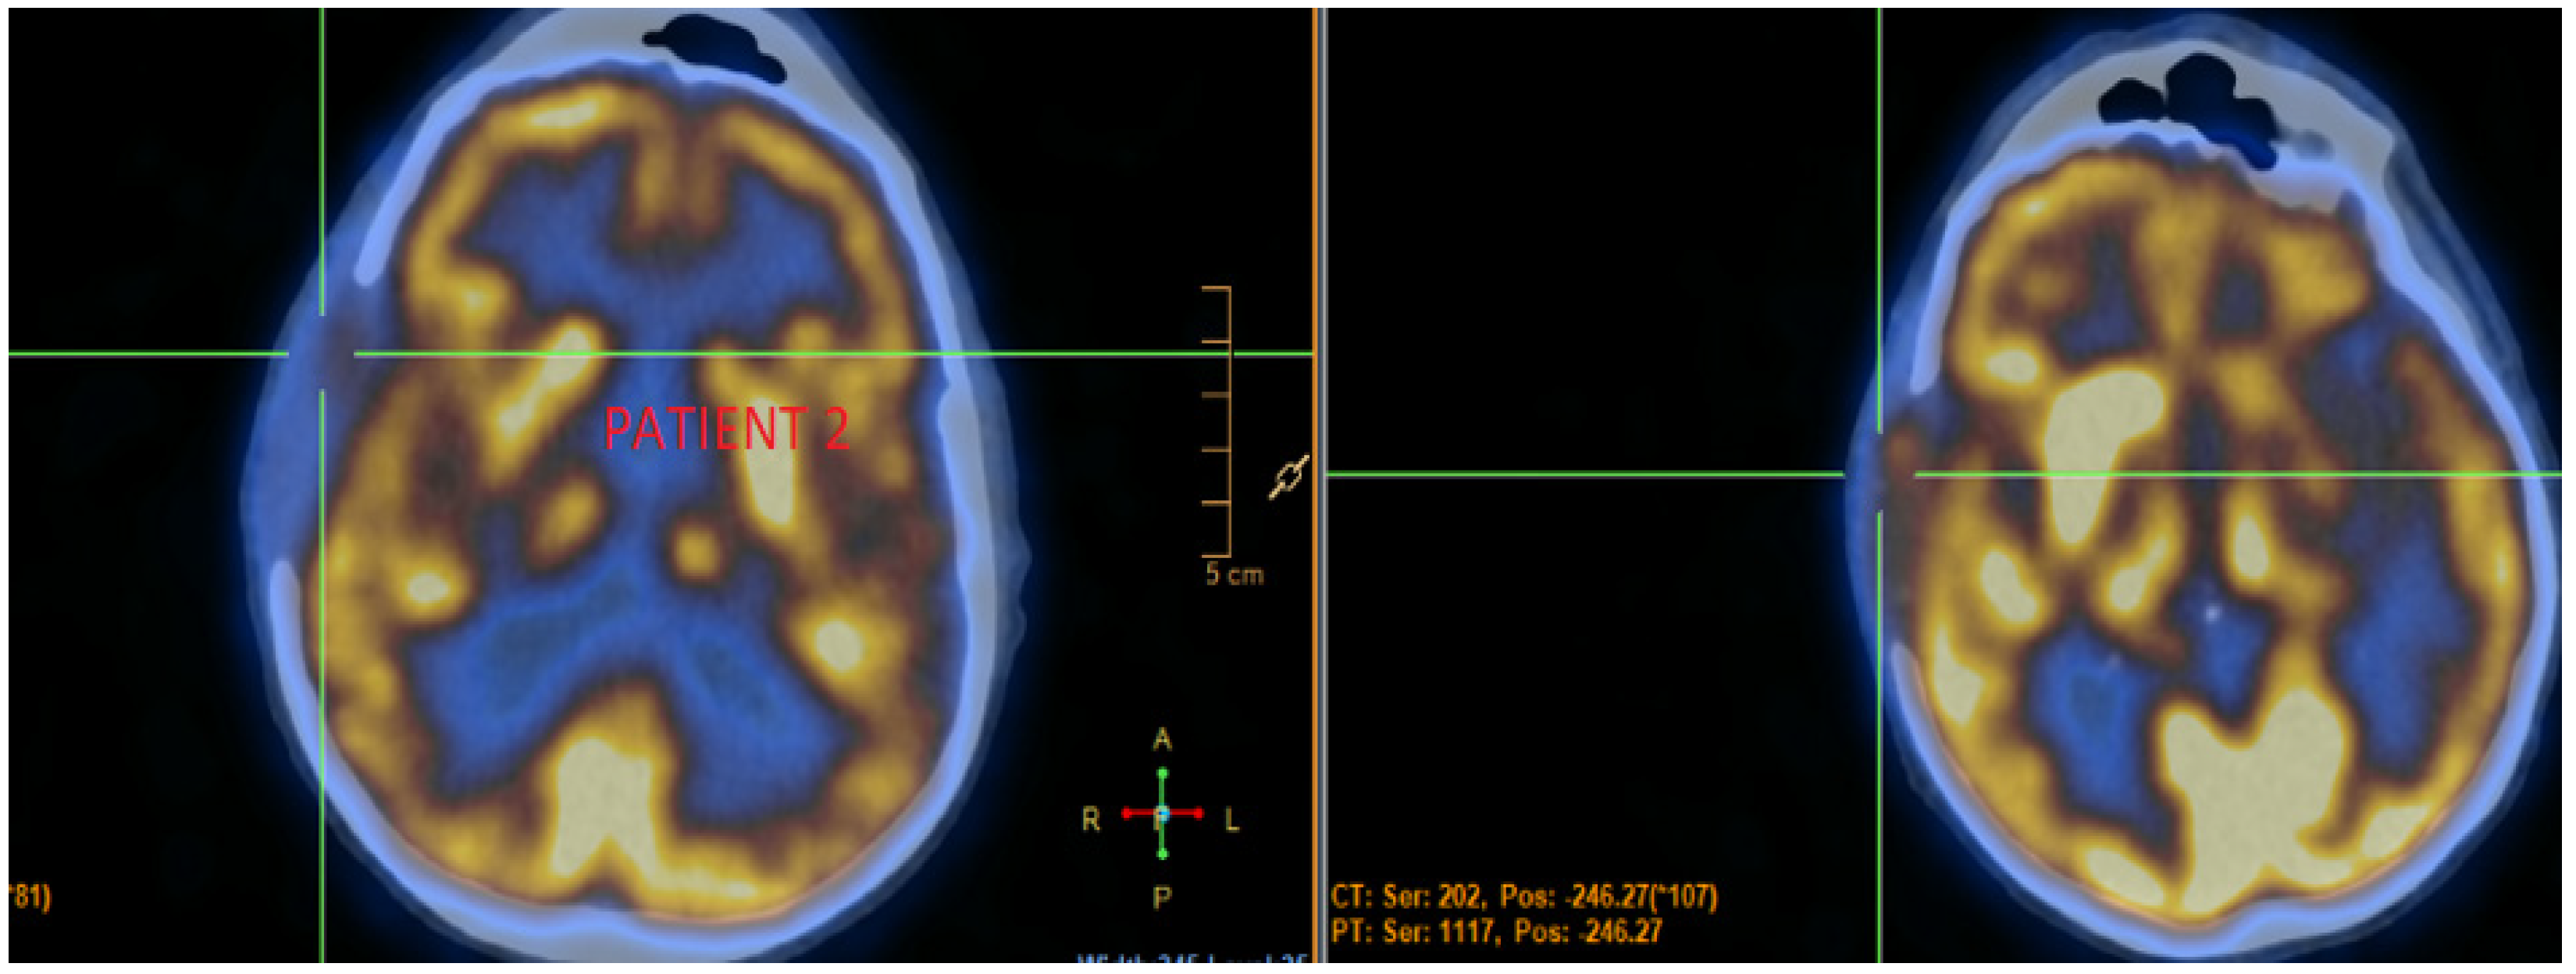

3.2. Case 2